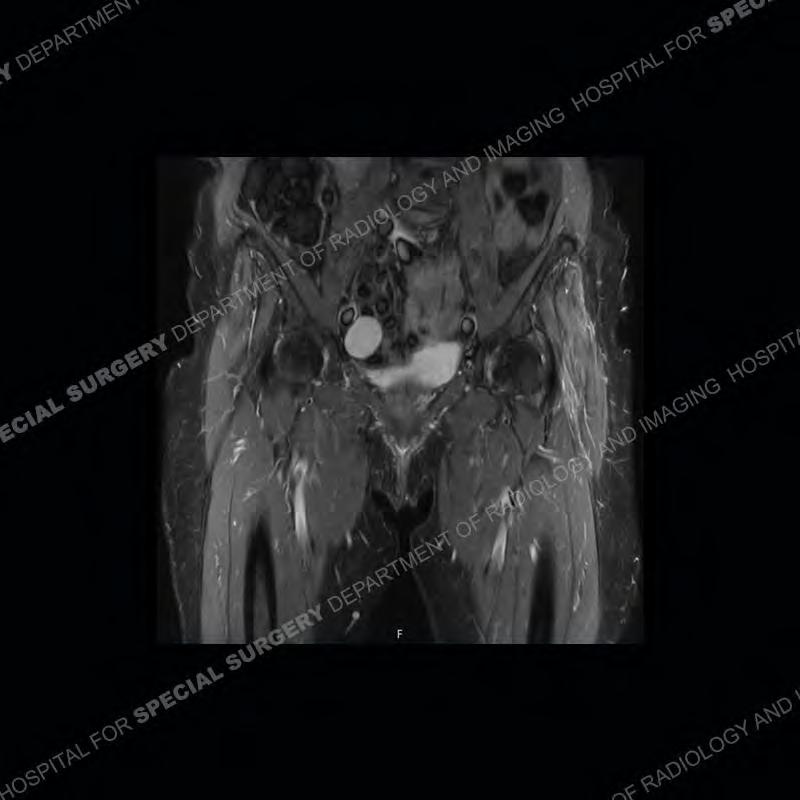

The radiograph is not particularly contributory in this case. The MRI demonstrates markedly abnormal architecture of the gluteus minimus and anterolateral band of the gluteus medius. Portions of the tendons are high signal, portions are highly attenuated, and portions are disrupted. A large, complex fluid collection is present in the adjacent soft tissue.

Diagnosis: Gluteal Tendinosis and Disruption with Complex Trochanteric Bursal Collection

Not as much of a diagnostic dilemma as many of the other cases shown but just a nice example of the pathology seen of the gluteal tendons and a cause of trochanteric pain. Although, frequently thought of in isolation, trochanteric bursitis or bursal thickening is much more commonly a reactive change to underlying pathology of the subjacent gluteal tendons. The gluteus medius is divided into a posterior band and an anterolateral band. Tendinosis and partial tearing very commonly will involve the gluteus minimus and especially the more posterior fibers and then propagate into the anterior lateral band of the gluteus medius. Involvement of the posterior band of the medius is much less common and engenders a marked degree of functional impairment.

The bursae about the greater trochanter can be a little bit confusing especially given the terminology. Trochanteric bursitis is implied to mean the subgluteus maximus bursa which is present deep to the maximus and just lateral/superficial to the trochanter. That is the bursa involved in this case. In this case the complexity of the bursa relates to the tendon tearing with inflammatory change and probably hemorrhage accounting for the complexity. Two other, less frequently involved bursa are also present. The subgluteus medius and subgluteus minimus bursa are found just deep to the named tendons. Although pathology does frequently follow the previously described pattern it is possible to have isolated pathology to either the medius or minimus.